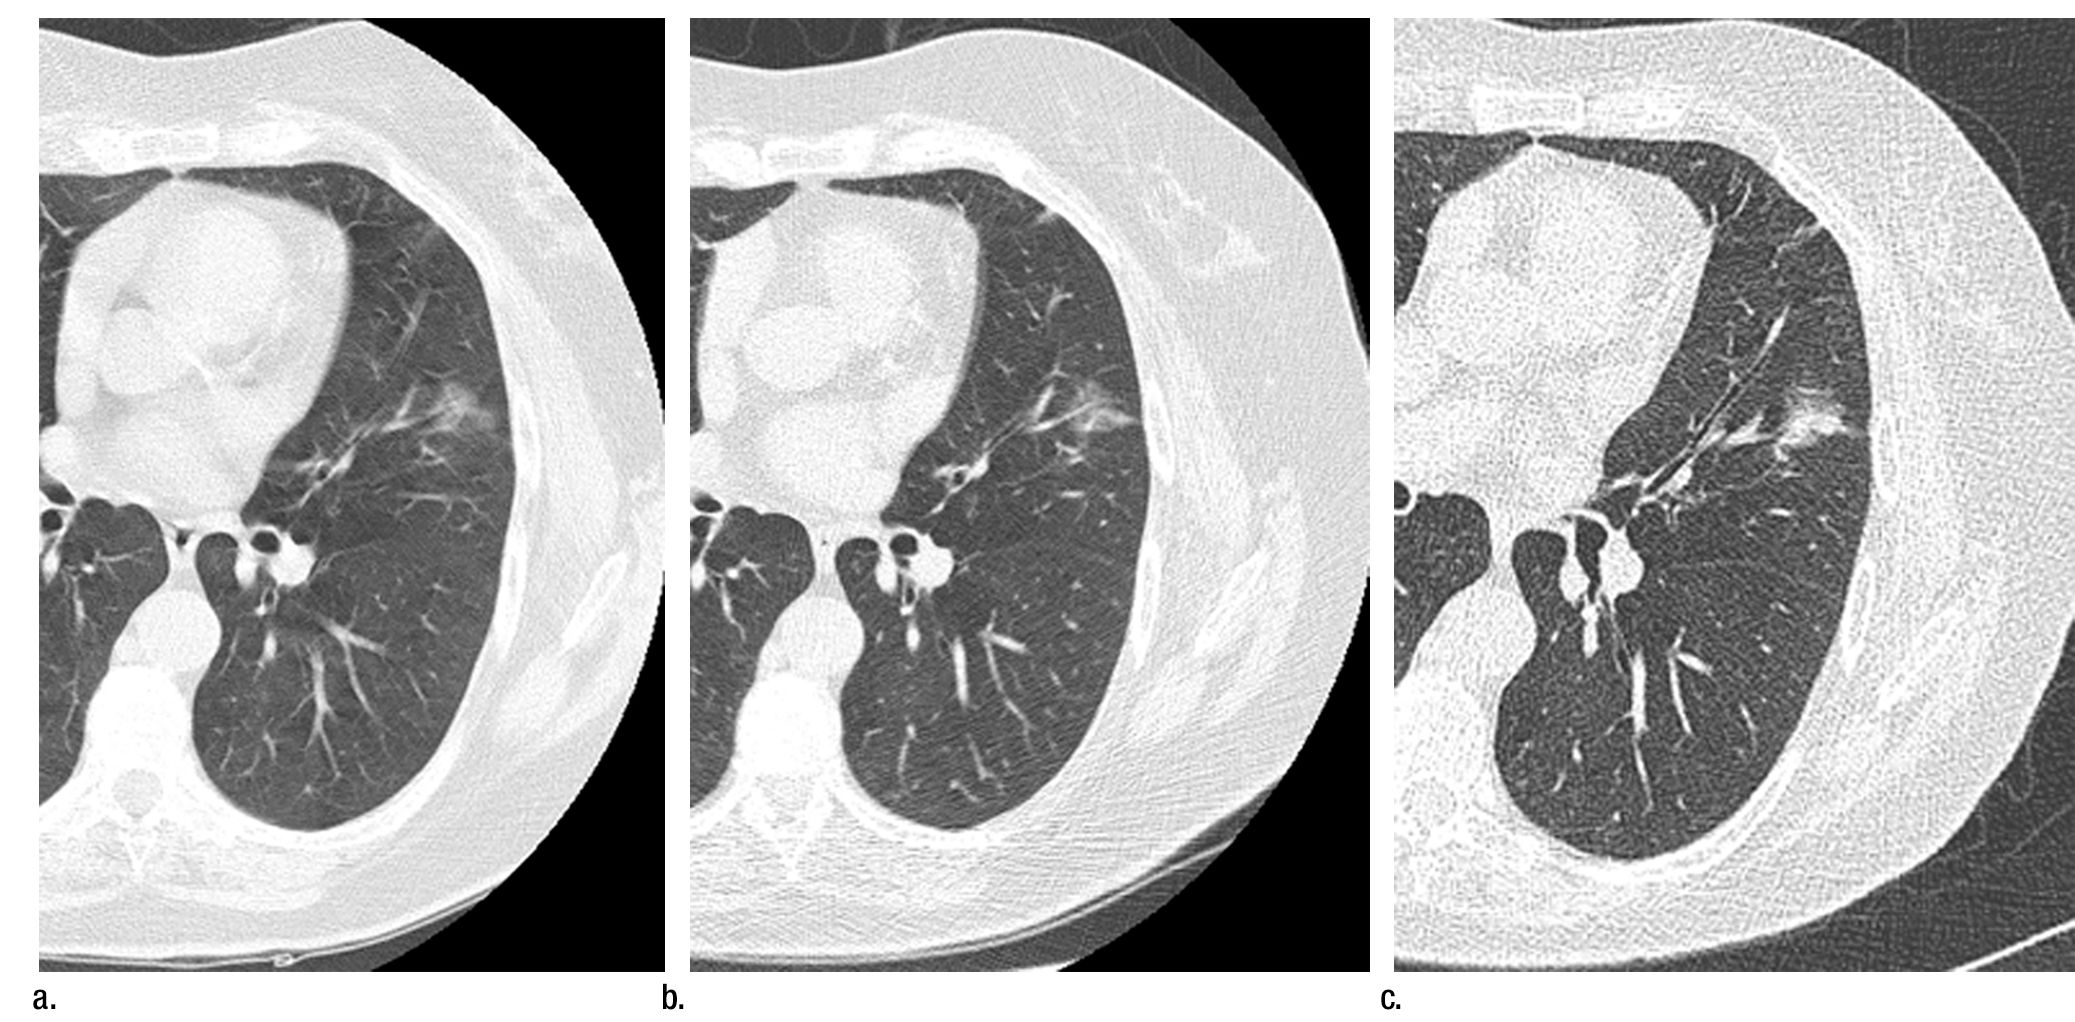

Case History: 60-year-old female with shortness of breath worsening with exertion and fatigue.

Follow-up LDCT screening for lung cancer decreases recall rates.